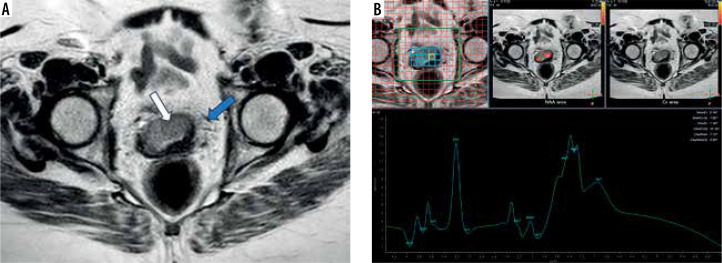

Material and methods: This prospective single-centre pilot study included 20 cases with pathologically proven cervical cancer. They underwent pelvic magnetic resonance imaging (MRI) with MRS. Two radiologists, blinded to the histopathological results, with 10 years of experience in gynaecological imaging, independently analysed the MRI images and MRS curves, and a third one resolved any disagreement. Using the histopathological results as a standard test, the receiver operating characteristics (ROC) curve was utilised to calculate the optimal lipid peak (1.3 ppm) cutoff for predicting high-grade cervical cancer. The difference in MRS metabolites between low- and high-grade cervical cancer groups was estimated using the Mann-Whitney test.

Results: The study included 11 high-grade and nine low-grade cervical cancer cases based on the histopathological evaluation. A lipid (1.3 ppm) peak of 29.9 was the optimal cutoff for predicting high-grade cervical cancer with 100% sensitivity, 77.8%, specificity, and 90% accuracy. Moreover, there was a significant difference between low- and high-grade cervical cancer cases concerning lipid peak at 0.9 ppm, lipid peak at 1.3 ppm, and the peak of choline with (p-value 0.025, 0.001, and 0.023), respectively.